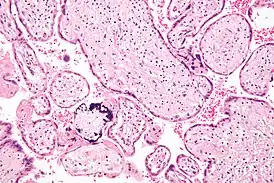

Инфекцию можно выявить микроскопически, путём обнаружения внутрядерных включений. При окраске гематоксилин-эозином тельца включений становятся темно-розовыми, их называют «совиными глазами».[9]

Микрофотография цитомегаловирусного плацентита.